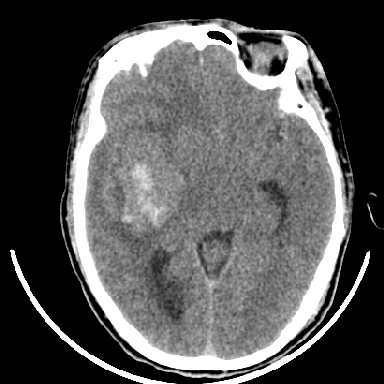

标题: CT6056:脑出血(血管畸形?) [打印本页]

标题: CT6056:脑出血(血管畸形?)

m 40突发头痛左侧偏瘫3小时

考虑高血压性脑出血,依据:

1是高血压性脑出血的好发部位,形态呈肾形,是高血压性脑出血的常见形状

2增强时占位效应加重了,考虑出血还没有停止

3病灶周围水肿不是太厉害,一般肿瘤出血水肿多非常明显

4病灶周围的‘软组织’影没有明显的强化

5至于脑血管畸形引起的出血,暂时没有看到明显的畸形血管影,也不太支持

支持右侧基底节脑出血

右侧基底节区脑出血.

支持右侧基底节区(主要为外囊区)原发性脑出血。

另附部分资料:“血液溢出血管外形成血肿,其内含有大量血红蛋白、血浆白蛋白,球蛋白,因这些蛋白对x线的吸收系数高于脑质,故ct呈现高密度阴影,ct值达40~90h,最初高密度灶呈非均匀一致性,中心密度更高,新鲜出血灶边缘不清。基底节区血肿多为“肾”型,内侧凹陷,外侧膨隆,因外侧裂阻力较小,故向外凸,其它部位血肿多呈尖圆形或不规则形”

术中抽出40ml陈旧血液,血肿底部似见一条索血管影